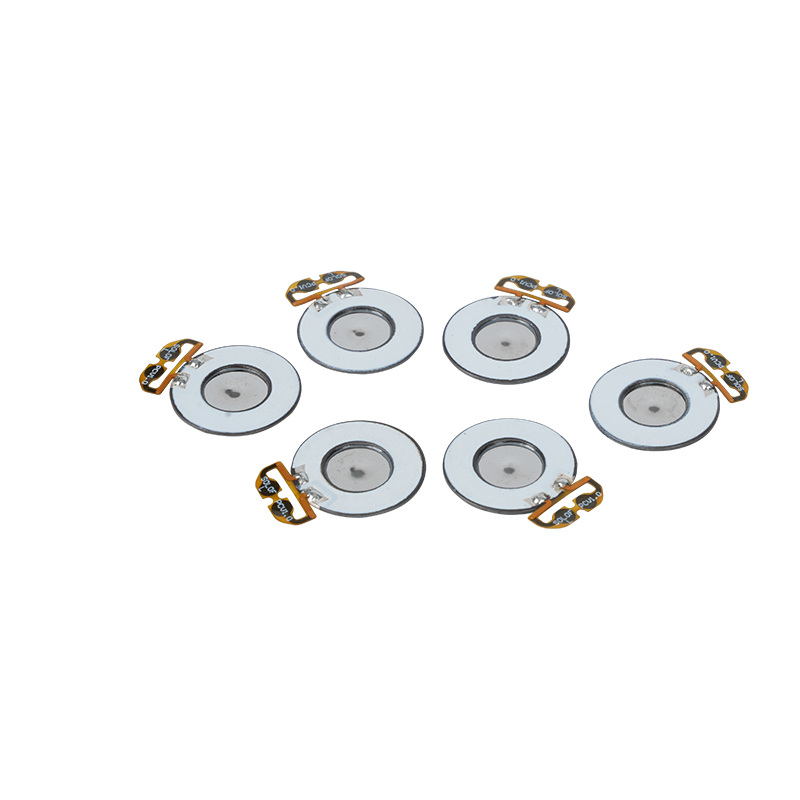

Medyczne tabletki do nebulizatora siatkowego to precyzyjne elementy stosowane w urządzeniach medycznych do przekształcania leków lub roztworów w drobne cząsteczki aerozolu w celu leczenia różnych chorób układu oddechowego, takich jak astma i przewlekła obturacyjna choroba płuc (POChP) itp., poprzez inhalację. Konstrukcja i dobór materiału arkusza nebulizatora mają kluczowe znaczenie dla zapewnienia skutecznego podawania leku i komfortu pacjenta. Arkusz membrany ze stali nierdzewnej jest dziurkowany w blasze stalowej tysiącami drobnych otworów o oczkach 2-3 μm za pomocą technologii wiercenia laserowego w precyzyjnym procesie laserowym, a następnie jest ściśle połączony z okrągłym arkuszem ceramicznym piezoelektrycznym, który przekształca częstotliwość rezonansową arkusza piezoelektrycznego w energię wibracji o wysokiej częstotliwości poprzez sygnał wyjściowy płytki sterownika PCB i szybko rozkłada płynny lek na drobne cząsteczki aerozolu. Krople te nazywane są również medianą wielkości cząstek. Gdy mediana wielkości cząstek D50 osiąga >60% lub więcej, cząstki będą wystarczająco małe, aby podczas oddychania móc dotrzeć głęboko do płuc do powierzchni pęcherzyków płucnych, poprawiając w ten sposób skuteczność wchłaniania leku i efekt terapeutyczny. Arkusz nebulizatora z mikrosiatką medyczną ma głównie kilka form, arkusz nebulizatora z mikrosiatką ze stali nierdzewnej, arkusz nebulizatora medycznego z niklowo-palladem, arkusz nebulizatora medycznego z polimeru PI i tak dalej. Wszystko powyższe odbywa się poprzez piezoelektryczną konwersję energii wibracji ceramicznych w celu osiągnięcia efektu atomizacji.

Poliimid (poliimid) określany jako PI to najlepsze kompleksowe działanie organicznych materiałów polimerowych, ma doskonałą stabilność chemiczną i może wytrzymać korozję różnych leków, aby zapewnić długotrwałe użytkowanie rozpylonych tabletek. Ponadto stabilność termiczna folii polimerowej PI jest również doskonała, przy długotrwałym stosowaniu w zakresie temperatur -200 ~ 300 ° C, wysokiej izolacji, ochronie środowiska i nietoksyczności, jako specjalny materiał inżynieryjny, szeroko stosowany w mikroelektronice lotniczej, membranach do separacji nano-ciekłych kryształów i innych dziedzinach, został włączony w XXI wieku przez kraje do jednego z najbardziej obiecujących materiałów inżynieryjnych i nie jest łatwo go osiągnąć zdeformowany w procesie dezynfekcji wysokotemperaturowej, aby mieć pewność, że produkt zostanie ponownie użyty! Ze względów seksualnych i bezpieczeństwa używamy technologii laserowej do perforacji laserowej, folii PI wszczepianej pomiędzy stal nierdzewną a arkusz piezoelektryczny, stosowania piezoelektrycznej ceramicznej technologii ultradźwiękowej, dzięki czemu rozpylone kropelki przez folię PI rozpraszają się w atomizacji cząstek o wielkości 3 ~ 4 μm do inhalacji nebulizacyjnej medycznej, bezpieczeństwo uwielbiane przez większość użytkowników, wykonane z nebulizatora z Główną zaletą PI jest brak zatykania, wewnętrzna ściana otworu jest gładka i zaokrąglona, brak pozostałości cieczy, atomizacja drobna i stabilna. Atomizacja jest delikatna i stabilna. Tabletki do nebulizacji z folią PI mogą skutecznie zapobiegać pozostałościom leków, zmniejszać ryzyko zanieczyszczenia krzyżowego. W praktyce odzwierciedlono również niskie zużycie energii przez tabletki do nebulizacji z membraną polimerową PI, podsumowując, tabletki do nebulizacji z membraną polimerową PI dzięki swoim doskonałym właściwościom użytkowym i zaletom konstrukcyjnym stały się nieodzowną częścią dziedziny medycznej terapii nebulizacyjnej.

Bezołowiowa ceramika piezoelektryczna jest znana jako „perła” przemysłu piezoelektrycznego, w przyszłości stopniowo zastąpi ona we wszystkich aspektach ceramikę piezoelektryczną na bazie ołowiu, która ma już tę samą wydajność piezoelektryczną, oraz blachę piezoelektryczną na bazie ołowiu. Jest całkowicie nietoksyczny, nieszkodliwy, bezpieczny i przyjazny dla środowiska, nie zawiera ołowiu, antymonu i innych metali ciężkich oraz innych pierwiastków objętych ograniczeniami Rohs, wysoka temperatura Curie Tc-328°C, bardzo niska strata elektryczna TangentLoss Dlatego bezołowiowy piezoelektryczny chip do atomizacji medycznej ma wielką wartość handlową i wartość uniwersalną, naprawdę nietoksyczną i przyjazną dla środowiska, bezołowiową ceramikę piezoelektryczną, a także niezanieczyszczającą, piezoelektryczną wydajność porównywalną z ceramiką na bazie ołowiu, stanie się popularną przyjazną dla środowiska ceramiką piezoelektryczną. Po latach badań i rozwoju, po ciągłych testach i eksperymentach, firmie udało się wyprodukować bezołowiowy medyczny chip atomizujący, który pozwala uzyskać taką samą ilość atomizacji jak chip atomizujący na bazie ołowiu, a także wymagania dotyczące cząstek o tej samej średnicy. Bezołowiowy chip nebulizatora medycznego Mesh z pewnością zabłyśnie i znajdzie szerokie zastosowanie.